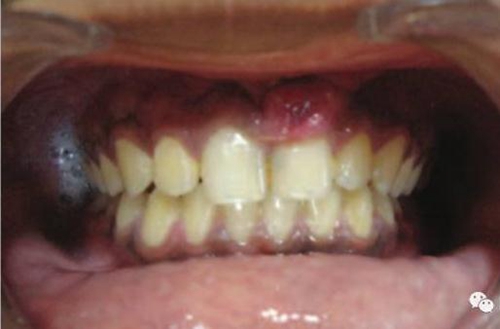

激光治療后即刻

治療前和2個(gè)月后效果對(duì)比